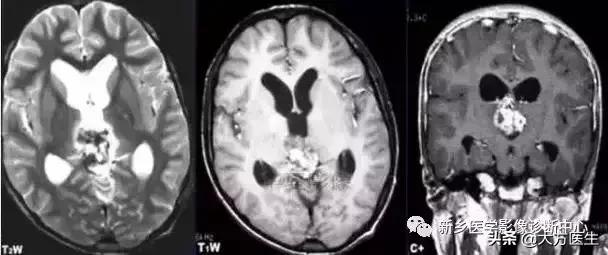

3、颅咽管瘤

多见于20岁以下,常有内分泌代谢障碍及视觉障碍,部分可有颅高压表现。

X:可见鞍区钙化,蝶鞍异常扩大及颅高压征象。CT:见囊实性肿块,囊壁斑块、蛋壳样钙化。MR:T1高等低混杂信号,T2为高信号。